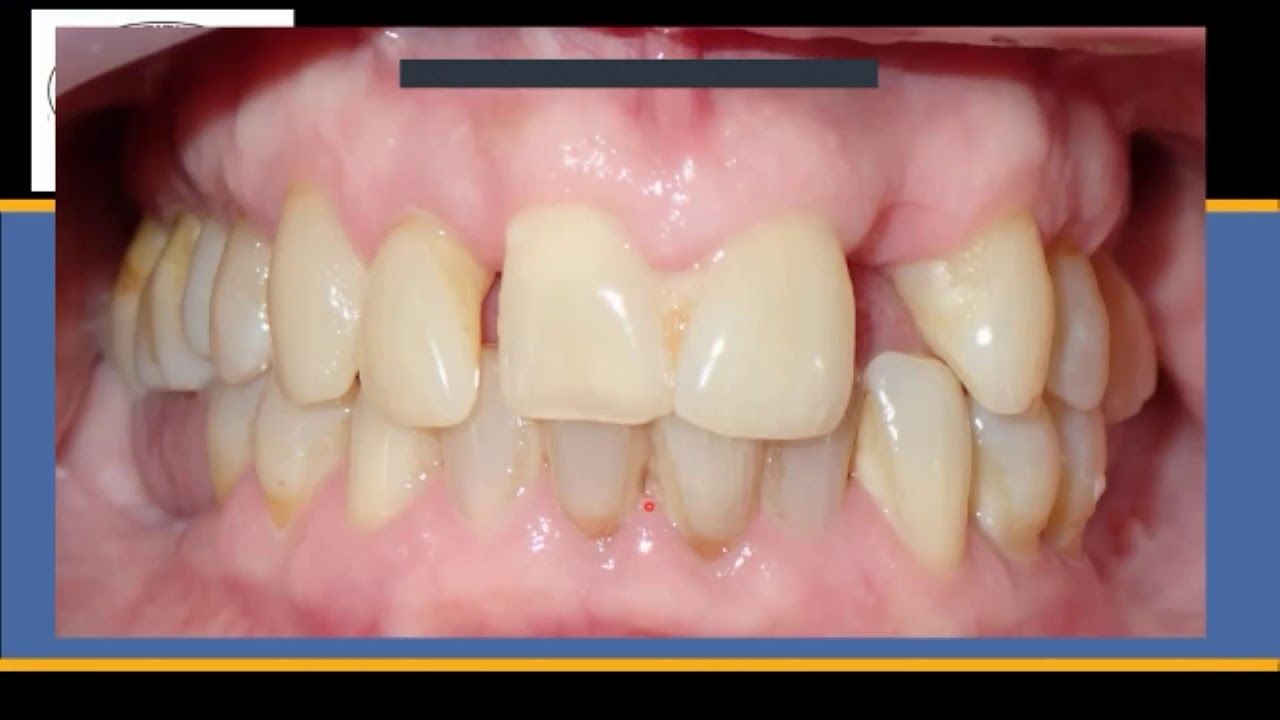

The Anxious, 1 Pack a Day, Gagging, Periodontal Nightmare

How do you treat this patient? It looks like she will lose all her upper teeth. Or will she? Let's look at how we can help this patient make the best decisions for herself.